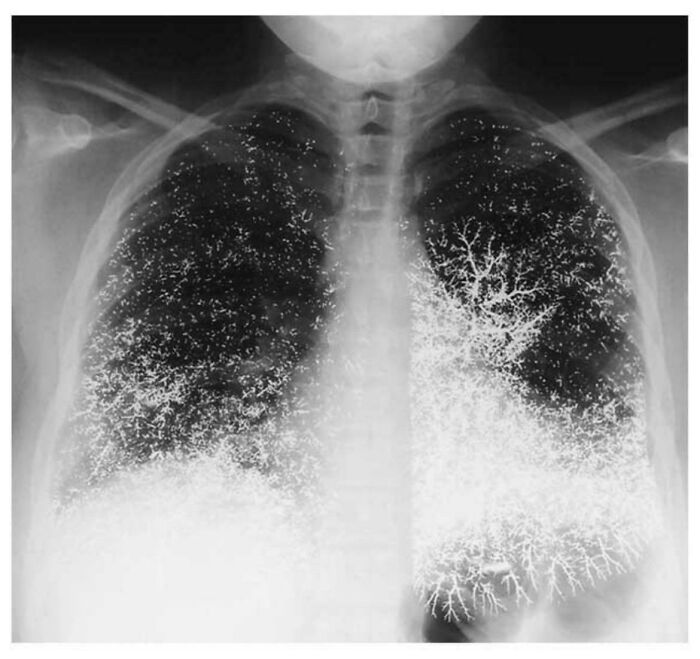

Chest X-Ray Of 21 Yr Old Dental Assistant After Attempting To Take Their Own Life By Intravenously Injecting Elemental Mercury